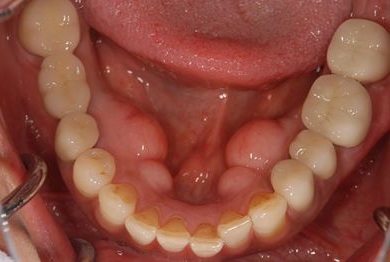

骨再生インプラント治療+セラミック治療+歯肉歯槽骨整形手術

| 治療内容 | インプラント2本(ソケットリフト、GBR)、メタルボンドセラミッククラウン3本、歯肉歯槽骨整形手術 | ||||||||||||||||||||||||||||||||